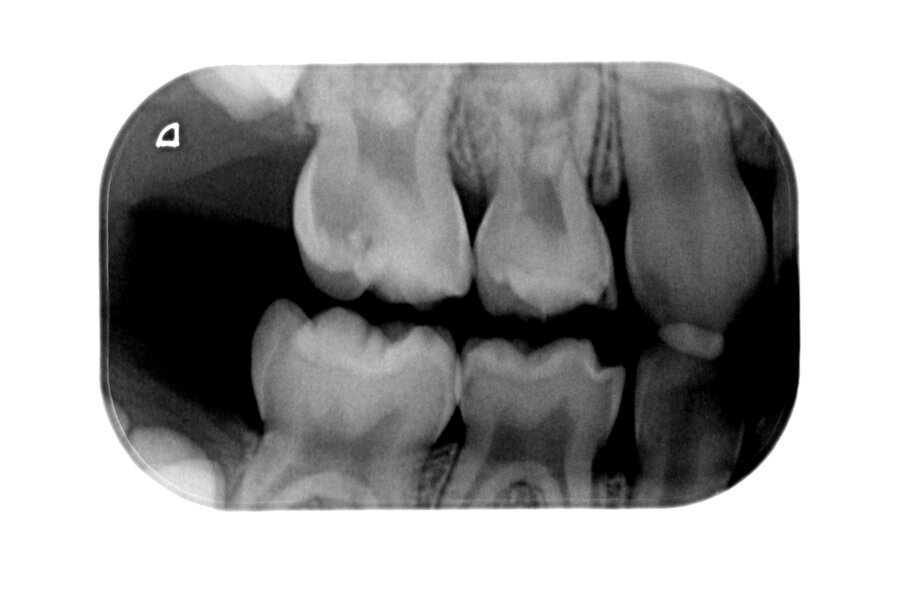

Afbeelding 12a-b. Casus 4: 21-02-18. BWR en BWL. Angstig meisje met pijn bij eten en poetsen bij 84 en 74.

Afbeelding 13a-b. Casus 4: 04-03-19. BWR en BWL na 1 jaar in 2 tempi middels de Hall-techniek succesvol zonder spuit, boor of angst behandeld.